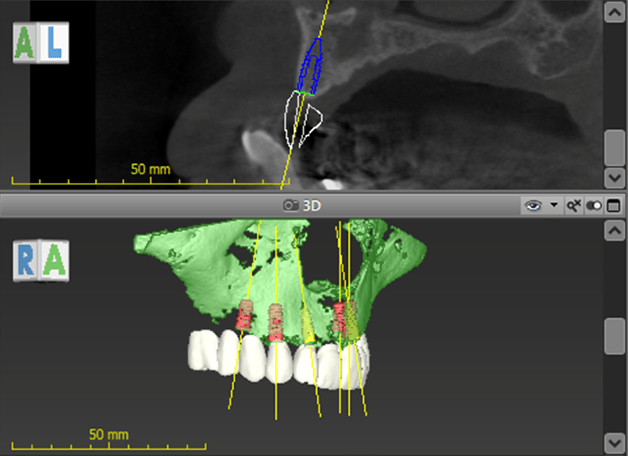

ガイデッドサージェリー(ガイド付き手術)

CTデータと口腔内の歯のデジタルスキャンデータを重ね合わせ、ドクターと放射線技師が骨の中でのインプラントの設置位置のシミュレーションを行います。それをもとに歯科技工士がガイデッドサージェリー用のテンプレート(サージカルガイド)を作製し、精度の高いインプラントオペを実施しています。このオペ様式により、術中と、術後の痛みの少ないインプラントオペが可能となります。